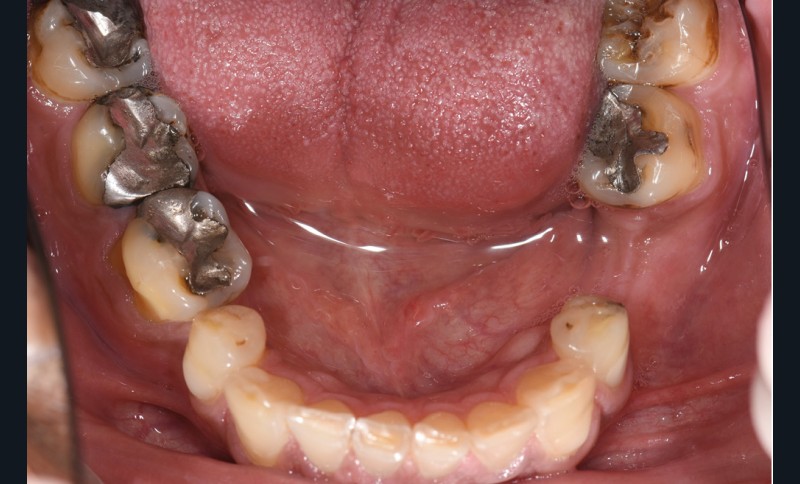

L’étiologie de cette usure est multifactorielle, revêtant une composante de type attrition (usure par contact dento-

dentaire), une composante abrasive avec un brossage traumatique et, en dernier lieu, une légère composante tribo-érosive de par une pratique importante de sport avec gel et boisson acide (fig. 1-4) [1].